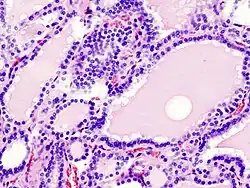

Die Vorstellungen zur Pathogenese der Struma haben sich in den letzten Jahrzehnten geändert. Bis in die Mitte der 1980er Jahre ging man davon aus, dass Jodmangel zu einer leichten Hypothyreose führe und dass nachfolgend die Hirnanhangsdrüse (Hypophyse) die Produktion des Hormons TSH erhöht, um die Schilddrüse zum Wachstum, zur Jodaufnahme und zur Schilddrüsenhormonproduktion zu stimulieren. Experimentelle Arbeiten an kultivierten Schilddrüsenzellen haben aber gezeigt, dass ein erhöhter TSH-Spiegel nur dann zur Proliferation der Schilddrüsenzellen (Thyreozyten) führt, wenn gleichzeitig innerhalb der Zellen ein Jodmangelzustand herrscht.

Heute können folgende Mechanismen als gesichert gelten: Jodarmes Schilddrüsengewebe setzt bestimmte Wachstumsfaktoren frei (den IGF, den EGF, den TNF-α und den FGF), die auf die freisetzenden Zellen selbst und ihr benachbartes Gewebe wirken (autokrine und parakrine Sekretion). Diese Faktoren führen zu einer Zellvermehrung (Hyperplasie) der Schilddrüsenfollikel, sowie zur Vermehrung bestimmter Bindegewebszellen (Fibroblasten) und zum Einsprießen von Blutgefäßen. Ausreichend mit Jod versorgte Thyreozyten produzieren hingegen die wachstumshemmenden Faktoren TGF-b und Jod-Lactone. Das TSH fördert zusätzlich das Wachstum der einzelnen Thyreozyten (Hypertrophie), ändert die Wirkung der einzelnen Wachstumsfaktoren aber durchaus in verschiedene Richtungen.

Diese Vorgänge sind zunächst nicht krankhaft, sondern dienen der normalen (physiologischen) Anpassung der Schilddrüse an Phasen eines relativen Jodmangels. Bei jahrelangem Jodmangel kommt es aber zu zusätzlichen degenerativen Veränderungen der Schilddrüse, in deren Verlauf knotige Veränderungen auftreten, sowie zur Bildung autonomer Areale, die sich vom Regelkreis zwischen Hypophyse und Schilddrüse abgekoppelt haben. Sie reagieren also nicht mehr auf die Steuerungsversuche des TSH.